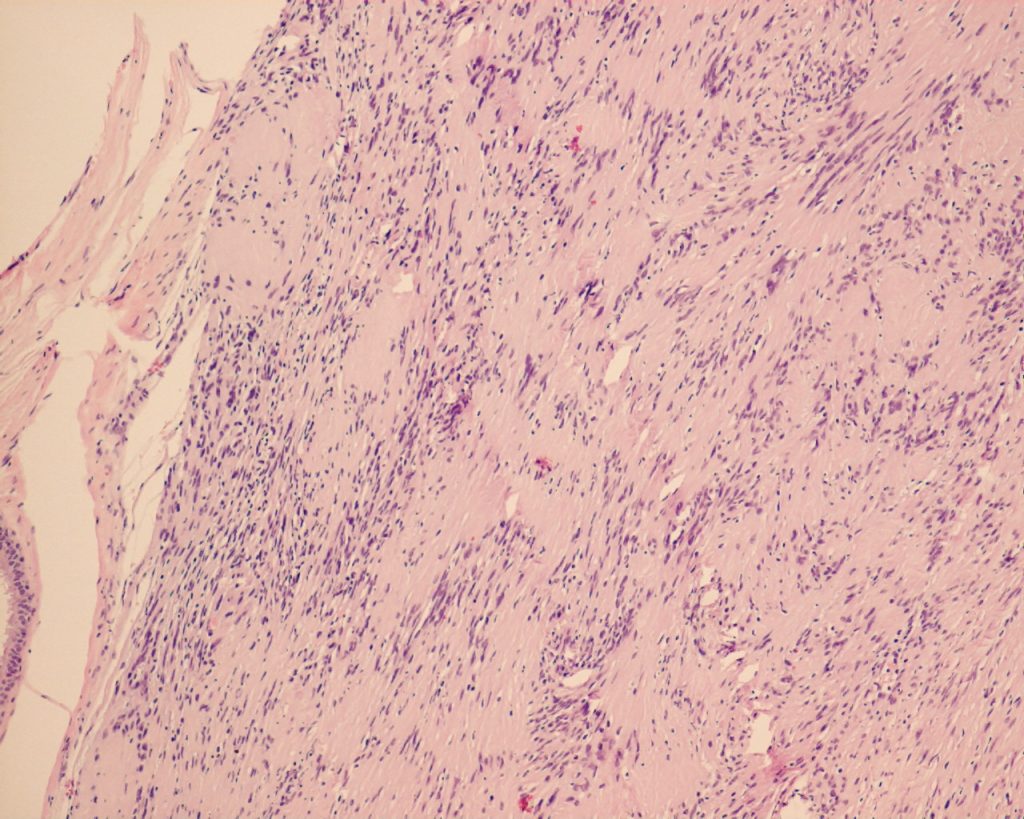

She was seen by cardiothoracic surgeon one year later, flexible bronchoscopy was repeated on 31 May 2011, it showed a roundish cystic mass obstructing LB6. Bronchial biopsy showed endobronchial schwannoma.(fig 3&4). Lt. thoracotomy with left lower lobectomy was done on 25 July 2011. Pathology showed endobronchial schwannoma with clear margins.

Pathologically, the tumour usually has a well-defined border. On high power view, it composed of spindle cells in compact palisading pattern. Schwannoma is negatively stained for collagen IV, although it may be positive around Schwann cells, and the strong diffuse staining for S100 protein confirmed the diagnosis of schwannoma.

Fig.3 (Above) Spindle cells in compact palisading pattern